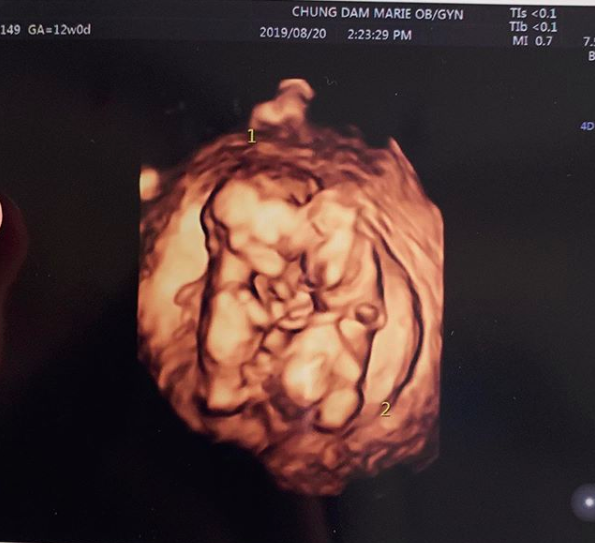

지난 28일 방송된 KBS2 예능 '살림하는 남자들 시즌2'(이하 살림남2)에서는 병원에서 쌍둥이 임신 소식을 확인하고 기뻐하는 최민환 율희 부부의 모습이 전파를 탔다.

이에 대해 박덕선 PD는 "최민환 율희 부부와 저희 제작진, 작가님들이 지속적으로 연락을 하는데 테스트기를 했을 때 연락을 주셔서 함께 병원에 가게 됐다. 저희 제작진이 대부분 엄마들이다. 이쯤 되면 안전에도 무리가 없다 싶은 날짜에 맞춰서 촬영을 진행했고, 아무래도 임신 초기는 위험하니까 방송도 어느 정도 크고 나서 내보내기로 했다. 그러다 보니 촬영 시점으로부터 한 달 뒤에 방송이 나가게 됐다"라고 설명했다.

그는 이어 최민환 율희 부부의 둘째가 쌍둥이라는 사실에 대해 "저희 모두 너무 놀랐다. 충격적이었다. 제작진이 이 부부를 참 좋아하는데, 둘째도 좋은 일인데 쌍둥이라고 하니 굉장히 복이 많은 친구들이라는 생각이 들었다. 공교롭게도 '살림남2' 방송 하루 전 출산율이 낮다는 기사가 나왔는데, 그렇게 보면 최민환 율희 부부는 애국자라는 생각도 들었다. 20대인데 아기가 벌써 3명이다"라며 함께 기뻐하기도.